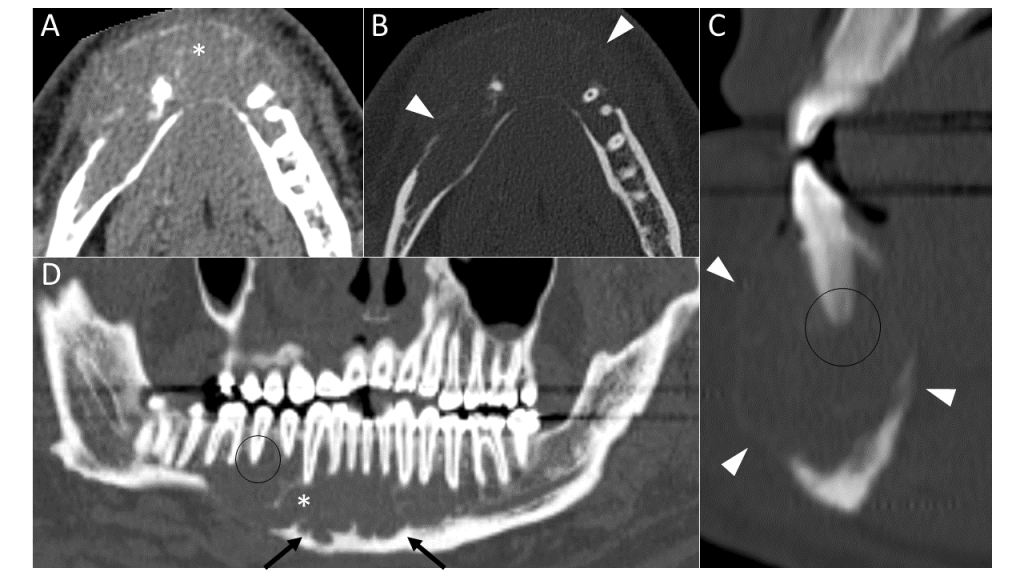

TC postcontraste en fase venosa con cortes axiales con filtro de partes blandas (A) y de hueso (B), reconstrucción sagital (C) y coronal curva (D) de hueso. Muestra una amplia masa tisular mandibular (asterisco), de bordes lobulados (flechas), que se extiende desde el cuerpo derecho hasta el izquierdo y expande y destruye la cortical ósea (puntas de flecha). Engloba múltiples raíces dentarias sin condicionar rizolisis (círculos). En su interior se identifican imágenes cálcicas lineales.

Granuloma de células gigantes central de la mandíbula

Típicamente se trata de una masa ósea localizada en la mandíbula o algo menos frecuente mente en el maxilar. Más raramente puede afectar huesos craneales o de extremidades. Por imagen se trata de una lesión de aspecto lobulado, de densidad partes blandas que realza tras la administración de contraste y que compromete expansión y remodelación ósea con focos de erosión cortical. Asimismo típicamente presenta focos de mineralización del componente tisular.